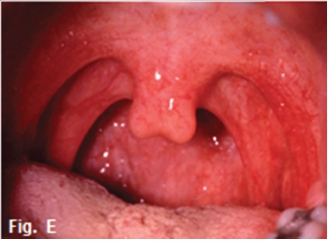

The above images are examples of cleft palate and cleft lip. After clubfoot, cleft lip and cleft palate are the most frequently encountered congenital deformities. Cleft palate is a defect in the continuity of the palate resulting from incomplete development or maturation of embryonal processes. It is often but not invariably accompanied by cleft lip. Cleft palate may be an isolated occurrence or may be part of various specific syndromes. Cleft palate varies greatly in severity and tissue involvement. The hard or soft palate, or a combination of both, can be affected. Frequently, clefts of the hard palate extend anteriorly through the alveolar ridge and lip, deviating to the right and/or left in the premaxilla. Sometimes, although much less often, the premaxillary defect is bilateral (Figs. A, B, C). When the alveolar ridge is affected, teeth in the region may be missing (Fig. D), deformed, or displaced, or supernumerary teeth can be present. The etiology is not completely understood, but heredity plays a role. Chromosomal abnormalities and exogenous factors are recognized as having etiologic impact, and a positive relationship between advancing age of parents and frequency of cleft has been demonstrated On occasion only the soft palate or a bifid uvula is involved (Fig. E). In unilateral cases of combined total cleft lip and palate, the vomer is in most cases connected with the palatal plate of the non-affected side In about half of cases, other developmental abnormalities are present. These include a variety of specific syndromes, congenital heart defects, polydactyly or syndactyly, hydrocephalus, spina bifida, and mental deficiency.